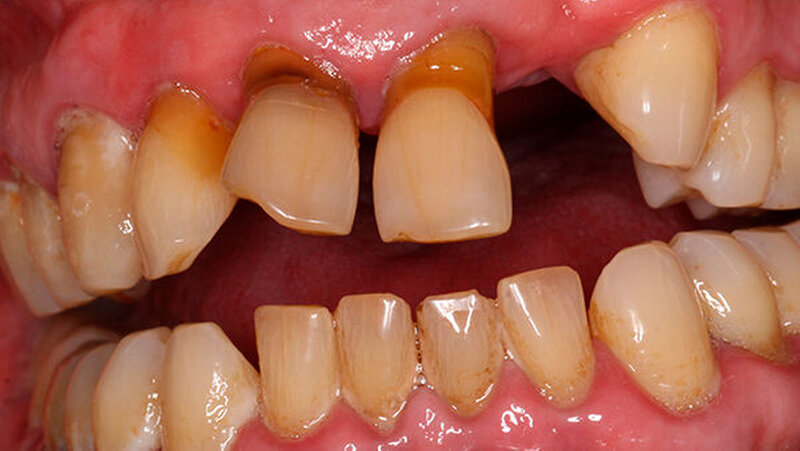

Für eine konventionelle brückenprothetische Versorgung scheiden die Schneidezähne ebenfalls aus: Zum langfristig prognostisch sicheren Ersatz des 22 wären Extraktionen und mehrere Substanz-opfernde Präparationen unausweichlich. Aufgrund des hohen Patientenalters und des Ausscheidens klassischer prothetischer Rehabilitationsmaßnahmen wird die Frontzahnlücke mit einer Adhäsivbrücke aus Metallkeramik versorgt (Abbildungen 3 und 4).

Durch die parodontal bedingte Elongation von 11 und 21 musste ein Kompromiss hinsichtlich der Gestaltung des Brückengliedes 22 im Hinblick auf dessen inzisale Ausdehnung erfolgen, so dass nun 23 kürzer ist als 22 (Abbildung 5). Ein halbes Jahr später befindet sich die Restauration unverändert in situ.